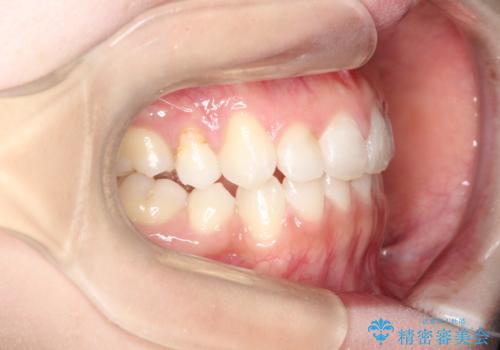

前歯の後戻りを部分矯正で整った歯並びへ

- 矯正治療後の上の前歯の後戻りを気にされて来院されました。

上の前歯のみにブラケットをつけて矯正治療を行いました。